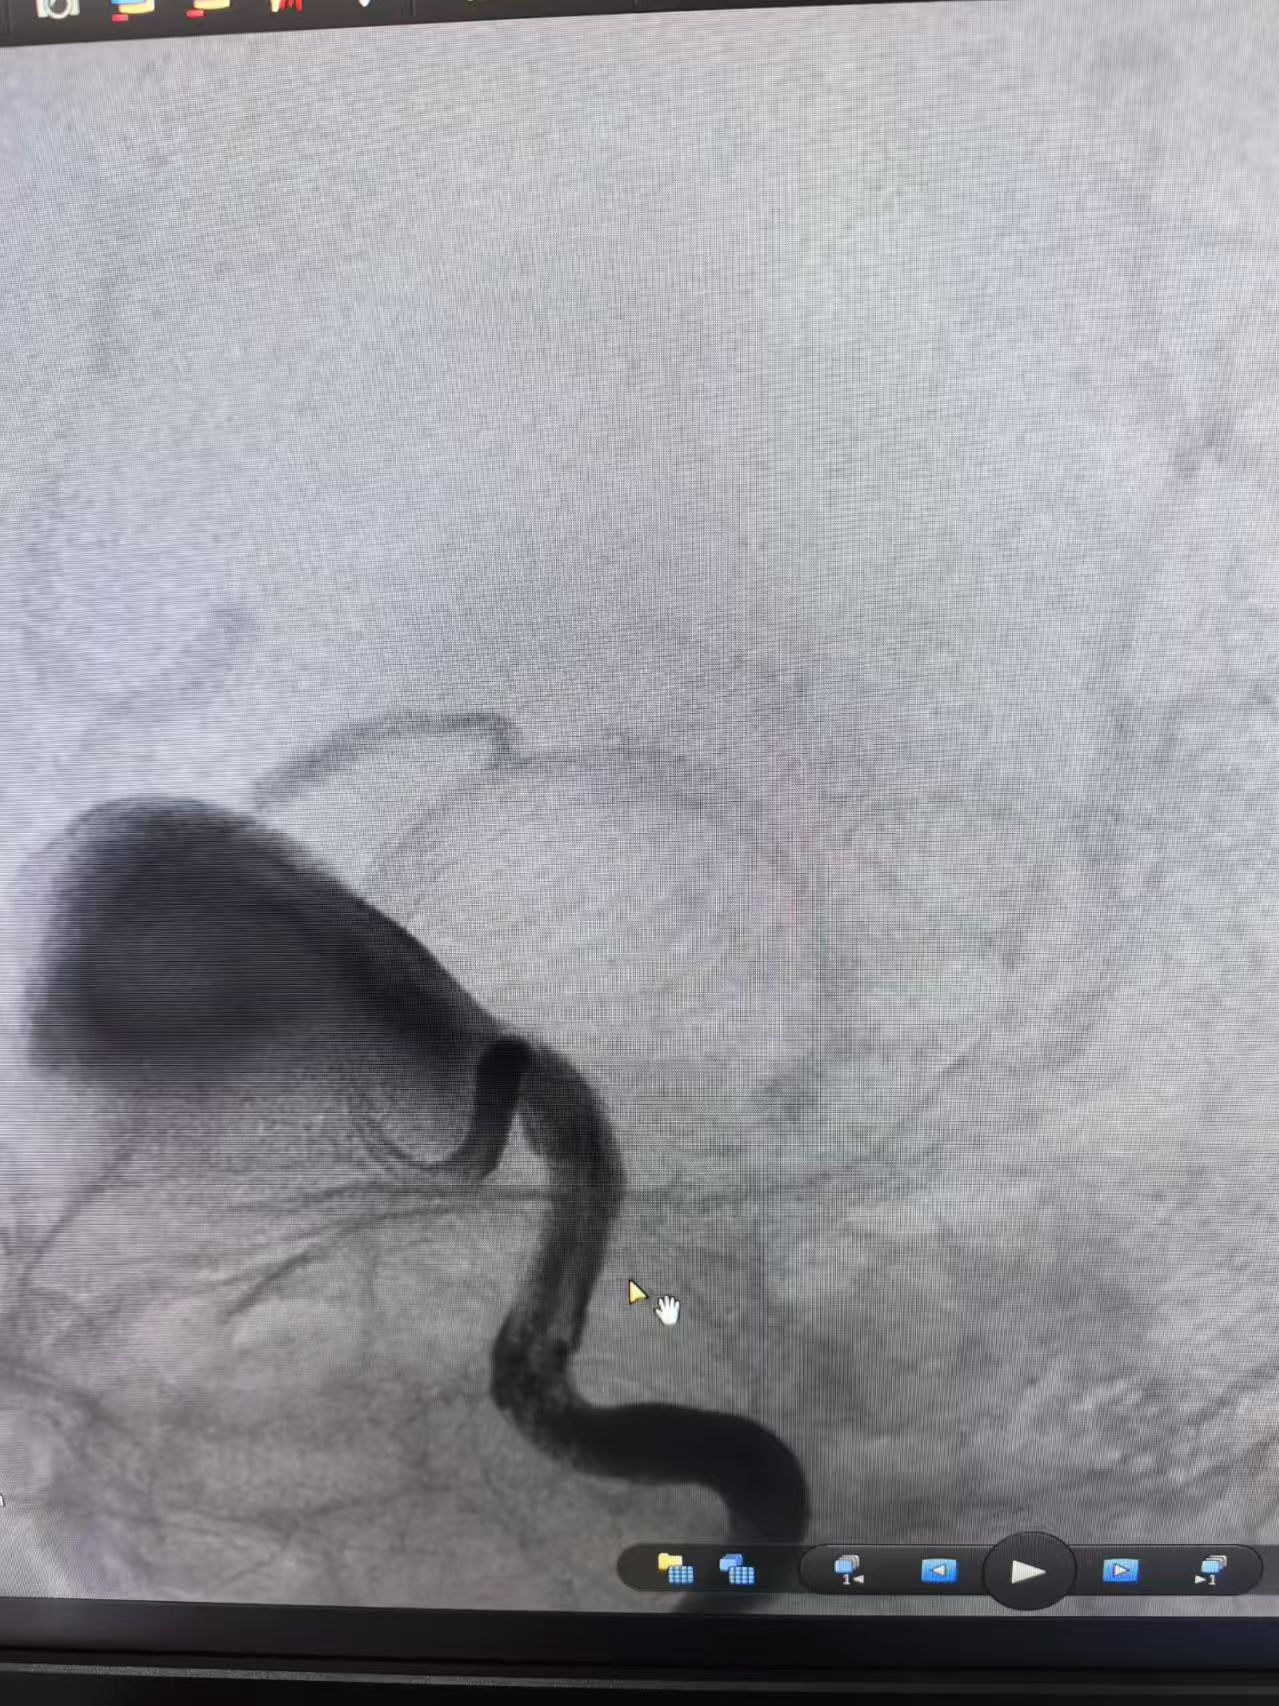

通常,动脉瘤直径≥25毫米(2.5cm)即可定义为巨大动脉瘤。而陈先生的动脉瘤直径达4cm,是标准巨大动脉瘤直径的1.6倍。此类动脉瘤因体积大、发病位置深,不仅易压迫周围脑组织及神经,破裂风险也远高于普通动脉瘤,治疗难度非常大,属于脑外科及脑病科领域的高危疾病。进一步完善脑血管造影提示动脉瘤形态不规则,瘤内喷射征明显,短期内破裂的风险巨大,随时可能引发颅内大出血,需尽快行手术治疗以消除破裂风险。随后,脑病科主任刘金城组织多学科会诊评估陈先生手术风险,制定手术方案。专家团队一致认为,陈先生颅内动脉瘤巨大,外科手术困难,传统支架辅助弹簧圈栓塞做到致密栓塞的可能性较小,唯一可能实现治愈的方式就是使用血流导向装置植入将血流导向远端,实现动脉瘤缓慢自愈。

针对如何将支架导管成功送去血管远端、如何将装置完美打开等难点问题,脑病科团队多次组织专题讨论,结合患者血管解剖特点制定详尽的手术预案。手术当日,刘金城及团队在全麻下行血流导向装置植入术,术中,因动脉瘤体积巨大、血管走行复杂,操作过程困难重重。得益于术前的充分准备,刘金城及团队精准运用导丝瘤内成攀超选、支架锚定微导管解攀等技术,成功将支架导管送到预定位置。随着血流导向装置打开并锚定在预定位置,运用推挤技术缓缓将血流导向装置顺利打开。为最大限度封堵动脉瘤流出道,刘金城采用两条血流导向装置重叠治疗,确保手术效果。术后陈先生苏醒顺利,未出现头痛、肢体麻木等特殊不适,目前已经顺利出院,视力恢复情况良好。